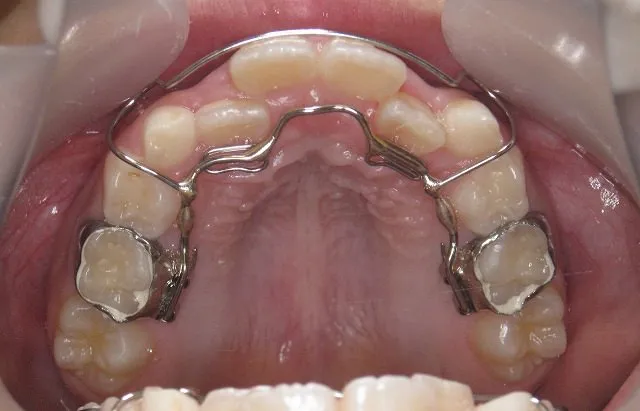

リンガルアーチ

歯の裏側に付けたブラケットにワイヤーを通して、歯を動かしていく装置です。歯の裏側に装着するので、装置が目立つようなことはありません。見た目を気にするお子様でも、安心して治療を受けて頂くことができます。ただし、お子様の歯の状態によっては使用できない場合もあります。